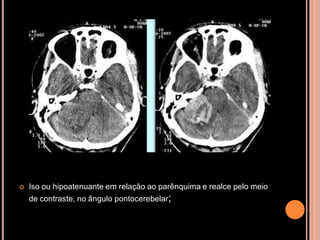

SCWHANNOMAS

Pequenas lesões no CAI, bem mais caracterizada

nas aquisições volumétricas(3D CISS);

Aspecto de “sorvete de casquinha” quando lesões

maiores com extensão pontocerebelar;

Hipo em T1 e hiper heterogêneo em T2;

Impregnação pelo Gd homogênea se pequenos e

heterogênea se grandes;

 Iso ou hipoatenuante em relação ao parênquima e realce pelo meio

de contraste, no ângulo pontocerebelar;